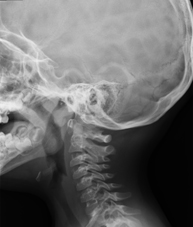

- Cervical spine X-ray

This technique uses X-ray rendered imaging for examining the cervical spine. Indicated for: trauma, cervical contracture, joint pain.

This technique uses X-ray rendered imaging for examining the cervical spine. Indicated for: trauma, cervical pain.